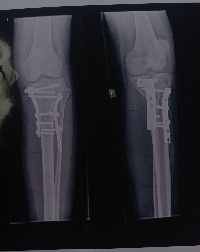

Olá, eu sou Júlia Vitória dos Santos Prado. Após um acidente, precisei passar por uma cirurgia na tíbia e na fíbula pelo SUS, mas um erro no procedimento agravou ainda mais a condição da minha perna.

Agora, com urgência, preciso de uma nova cirurgia corretiva para recuperar os movimentos e evitar complicações futuras. Infelizmente, o custo é elevado e o tempo é curto, por isso conto com a sua ajuda nessa vaquinha: qualquer valor já faz uma diferença imensa e me aproxima da recuperação.